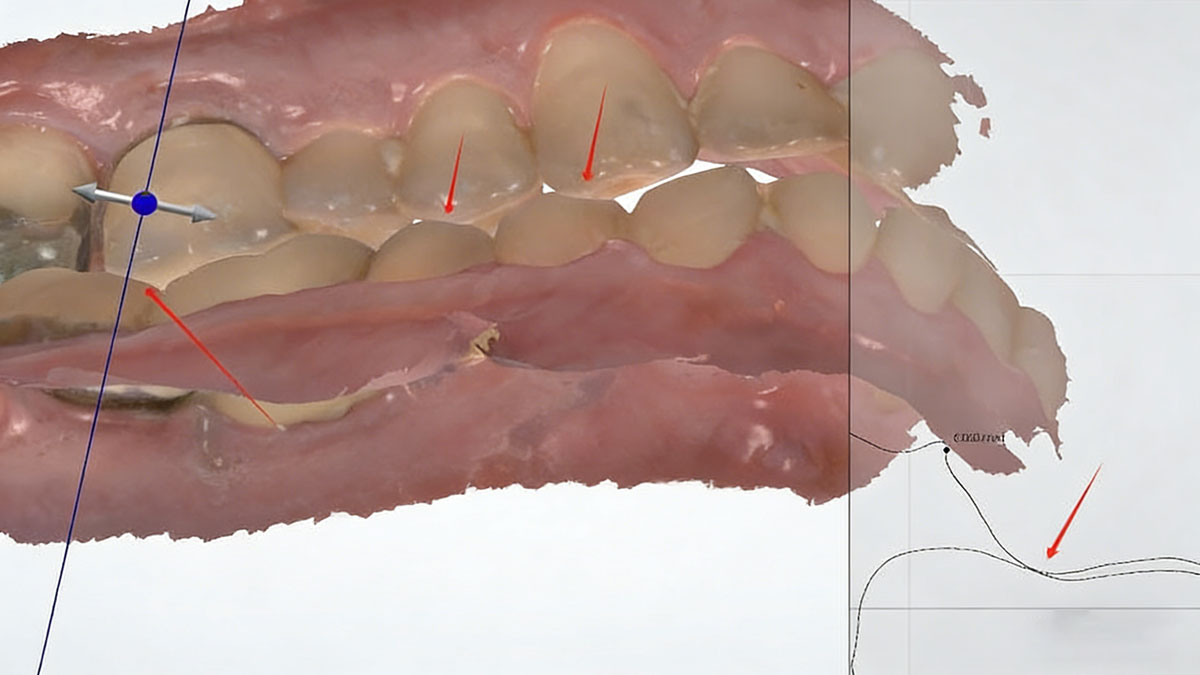

Ideally, your scans should come to our dental lab like this. There is a correct bite relationship between the upper scan and lower scan: the upper teeth can slightly touch the lower teeth. The measurement also shows that the gap between upper and lower is 0.000 mm. With such bite, we can always make a crown with perfect occlusion.